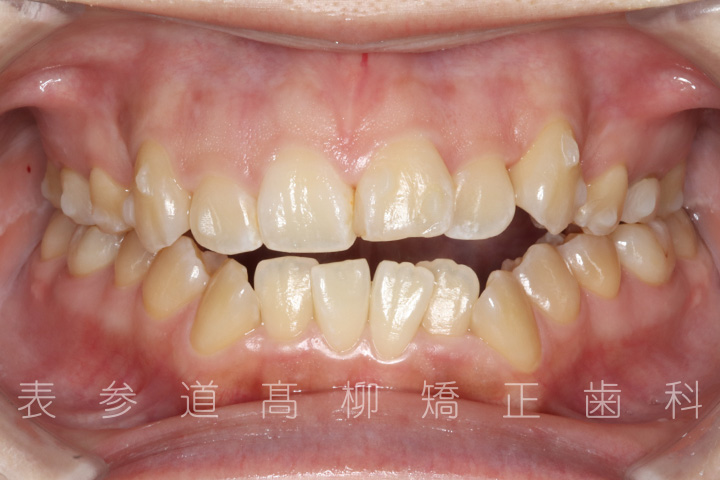

前歯のガタガタ感と開咬でお悩みの患者様の症例をご紹介いたします。

・前歯部開咬

・上下前歯部叢生(凸凹歯並び)

術前術後の比較